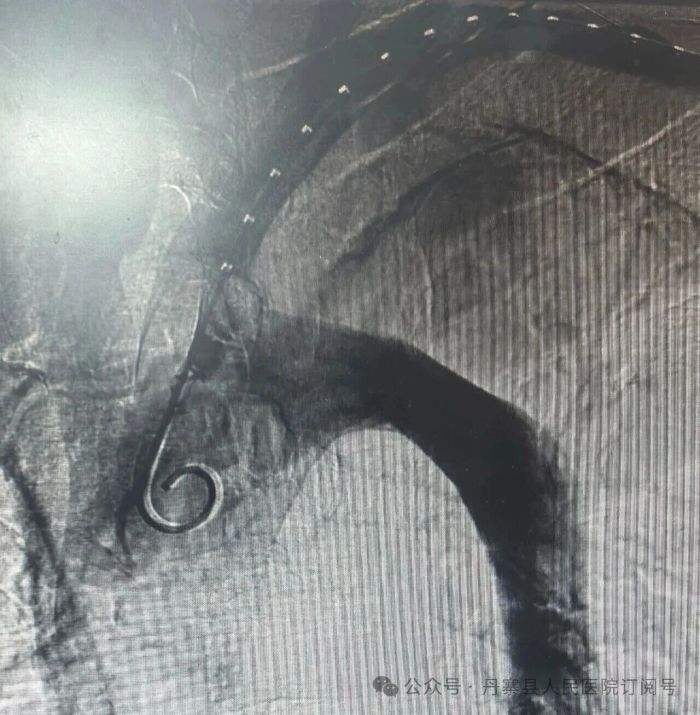

团队立即启动应急预案,经多学科紧急研判后一致决定:必须争分夺秒,在建立生命通道的同时优先处理最大风险。 团队当机立断,在镇静镇痛监护下为患者实施手术。该方案使患者在清醒状态下接受微创介入,既规避了等待全麻的时间延误,又显著降低了对循环系统的生理干扰。手术仅通过大腿根部的股动脉穿刺,将覆膜支架精准输送至主动脉破口处释放,成功封堵夹层,使血流恢复正轨。

手术在介入室内顺利完成,术后患者恢复良好,目前已康复出院。